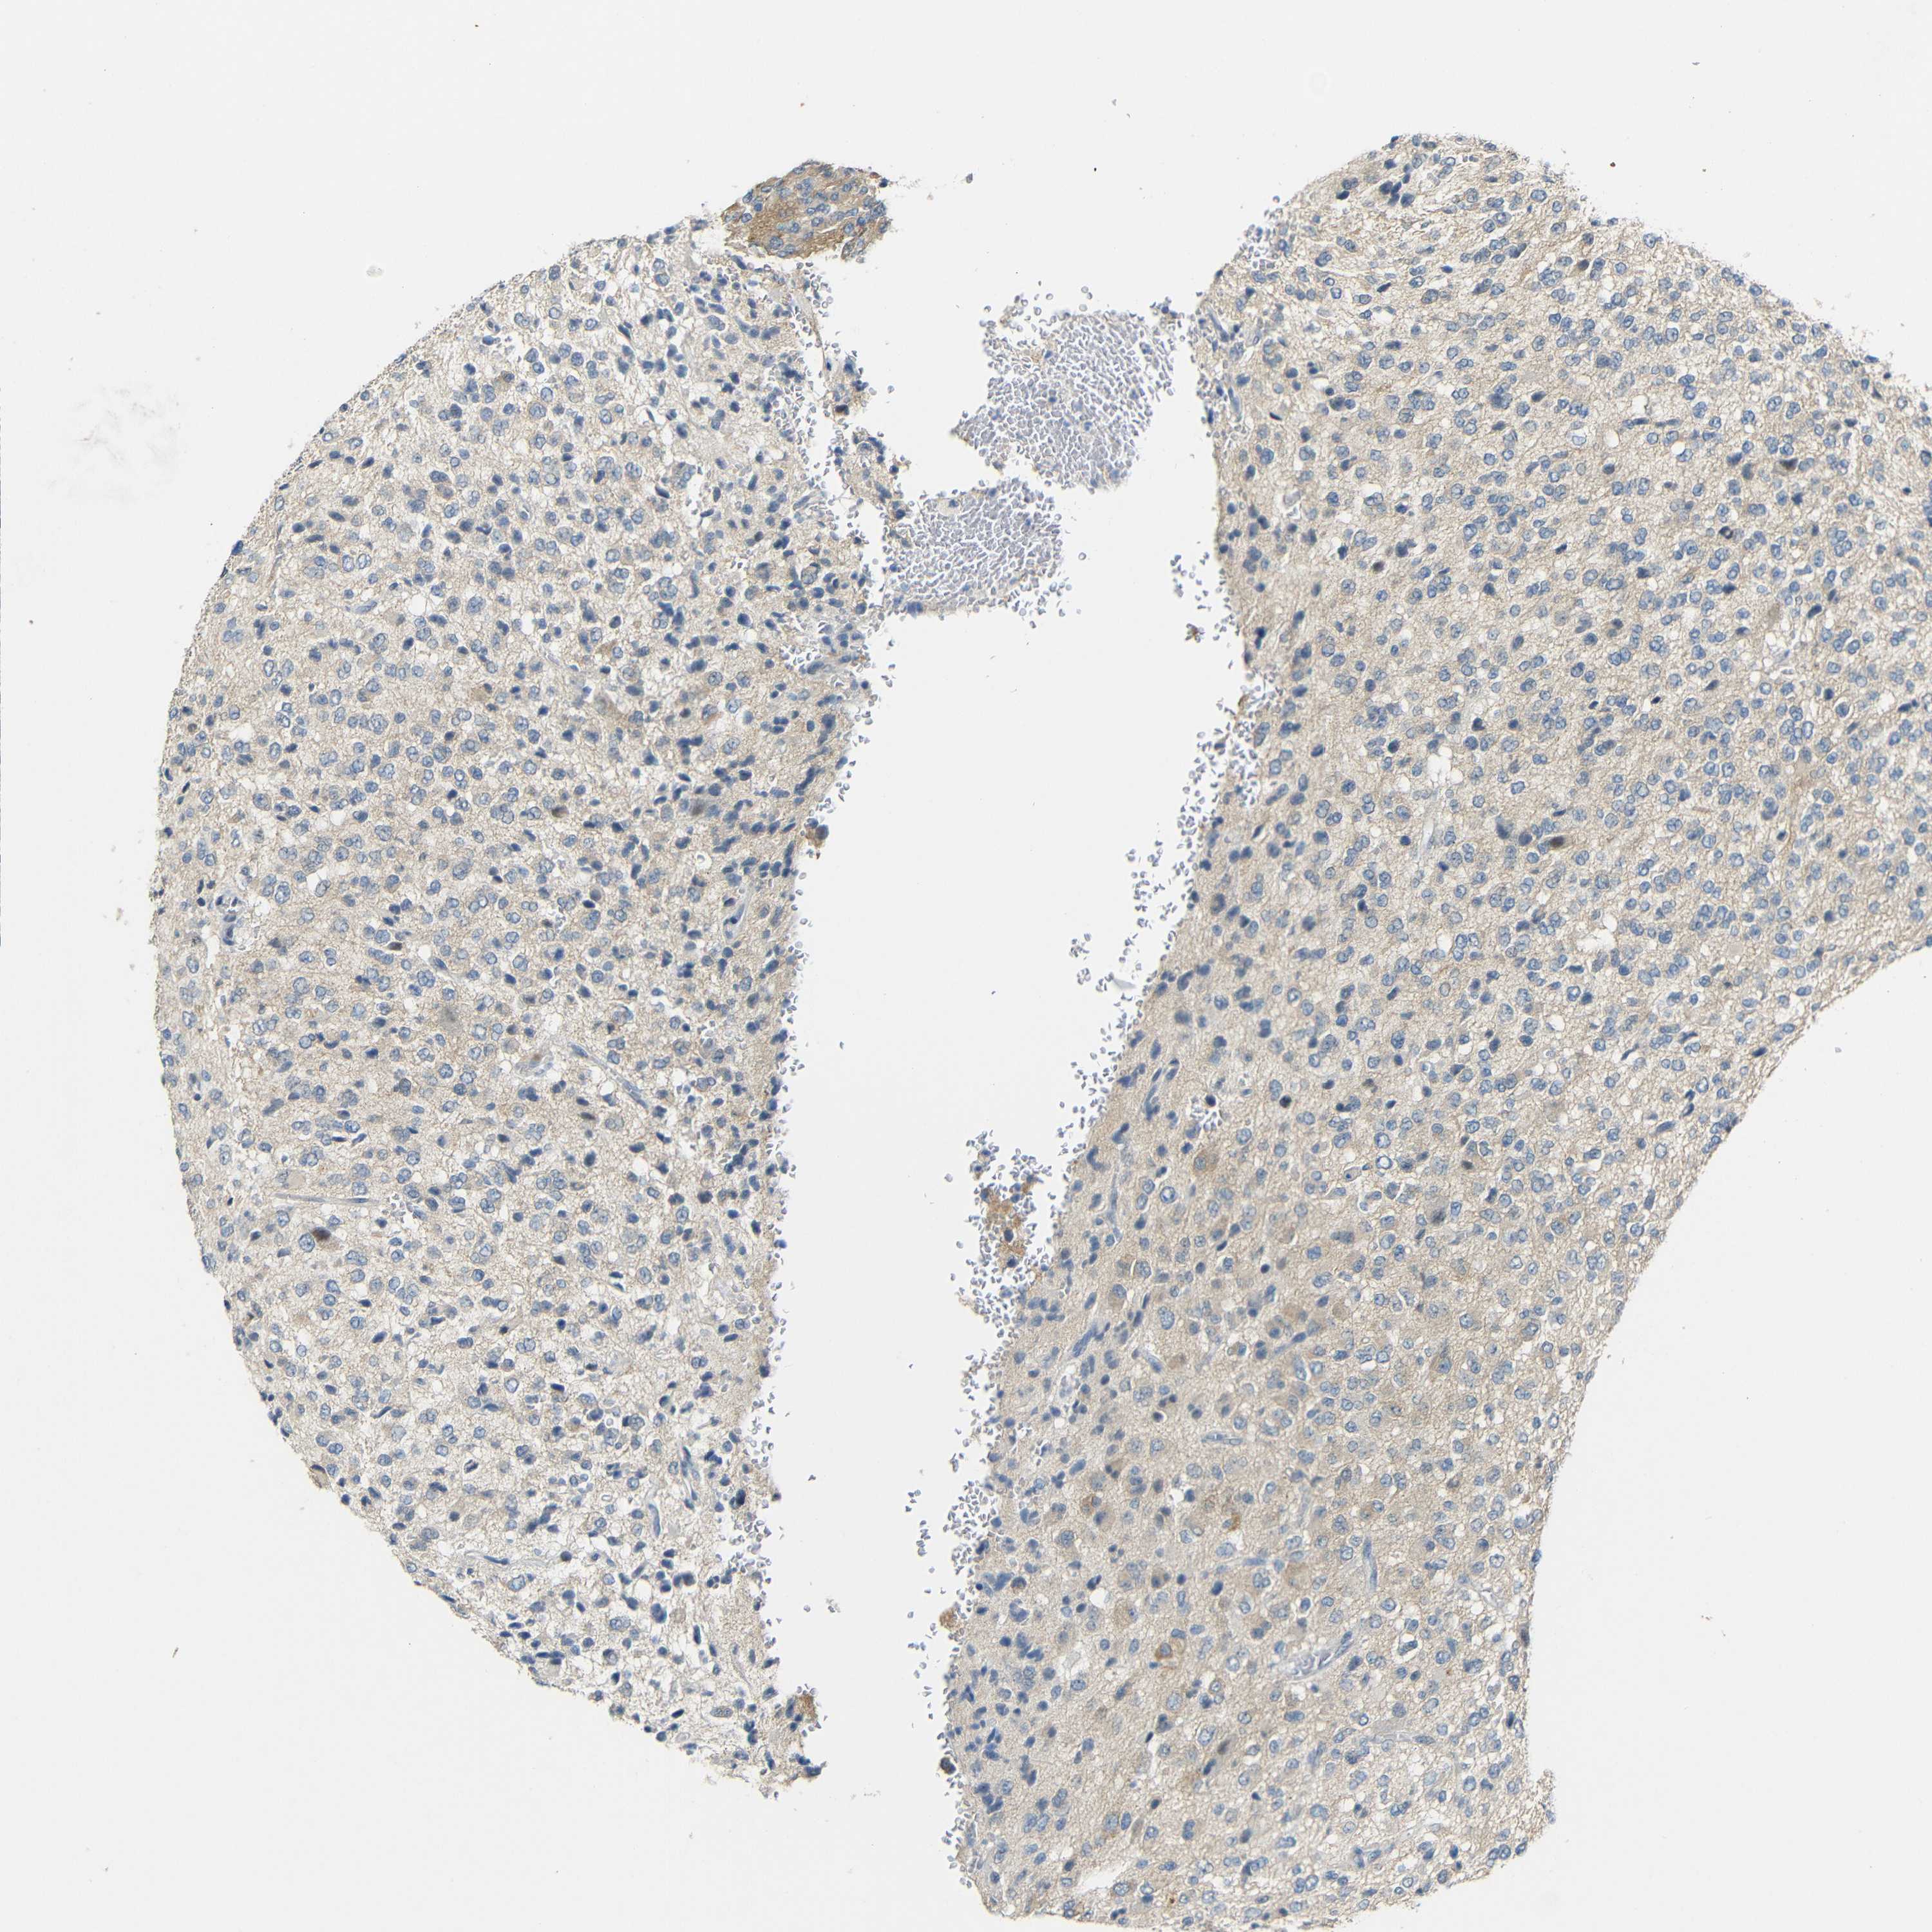

GLIOMA - Protein expressioni

A mouse-over function shows sample information and annotation data. Click on an image to view it in a full screen mode. Samples can be filtered based on level of antibody staining by selecting one or several of the following categories: high, medium, low and not detected. The assay and annotation is described here.

Note that samples used for immunohistochemistry by the Human Protein Atlas do not correspond to samples in the TCGA dataset.

Antibody stainingi

Antibody staining in the annotated cell types in the current human tissue is reported as not detected, low, medium, or high, based on conventional immunohistochemistry profiling in selected tissues. This score is based on the combination of the staining intensity and fraction of stained cells.

Each image is clickable and will lead to virtual microscopy that enables deeper exploration of all samples and also displays staining intensity scores, fraction scores and subcellular localization as well as patient and tissue information for each sample.

Antibody HPA013185

Staining

High

Medium

Low

Not detected

Intensity

Strong

Moderate

Weak

Negative

Quantity

>75%

75%-25%

<25%

None

Location

Nuclear

Cytoplasmic/membranous

Cytoplasmic/membranous,nuclear

Glioma, malignant, High grade

Glioma, malignant, Low grade